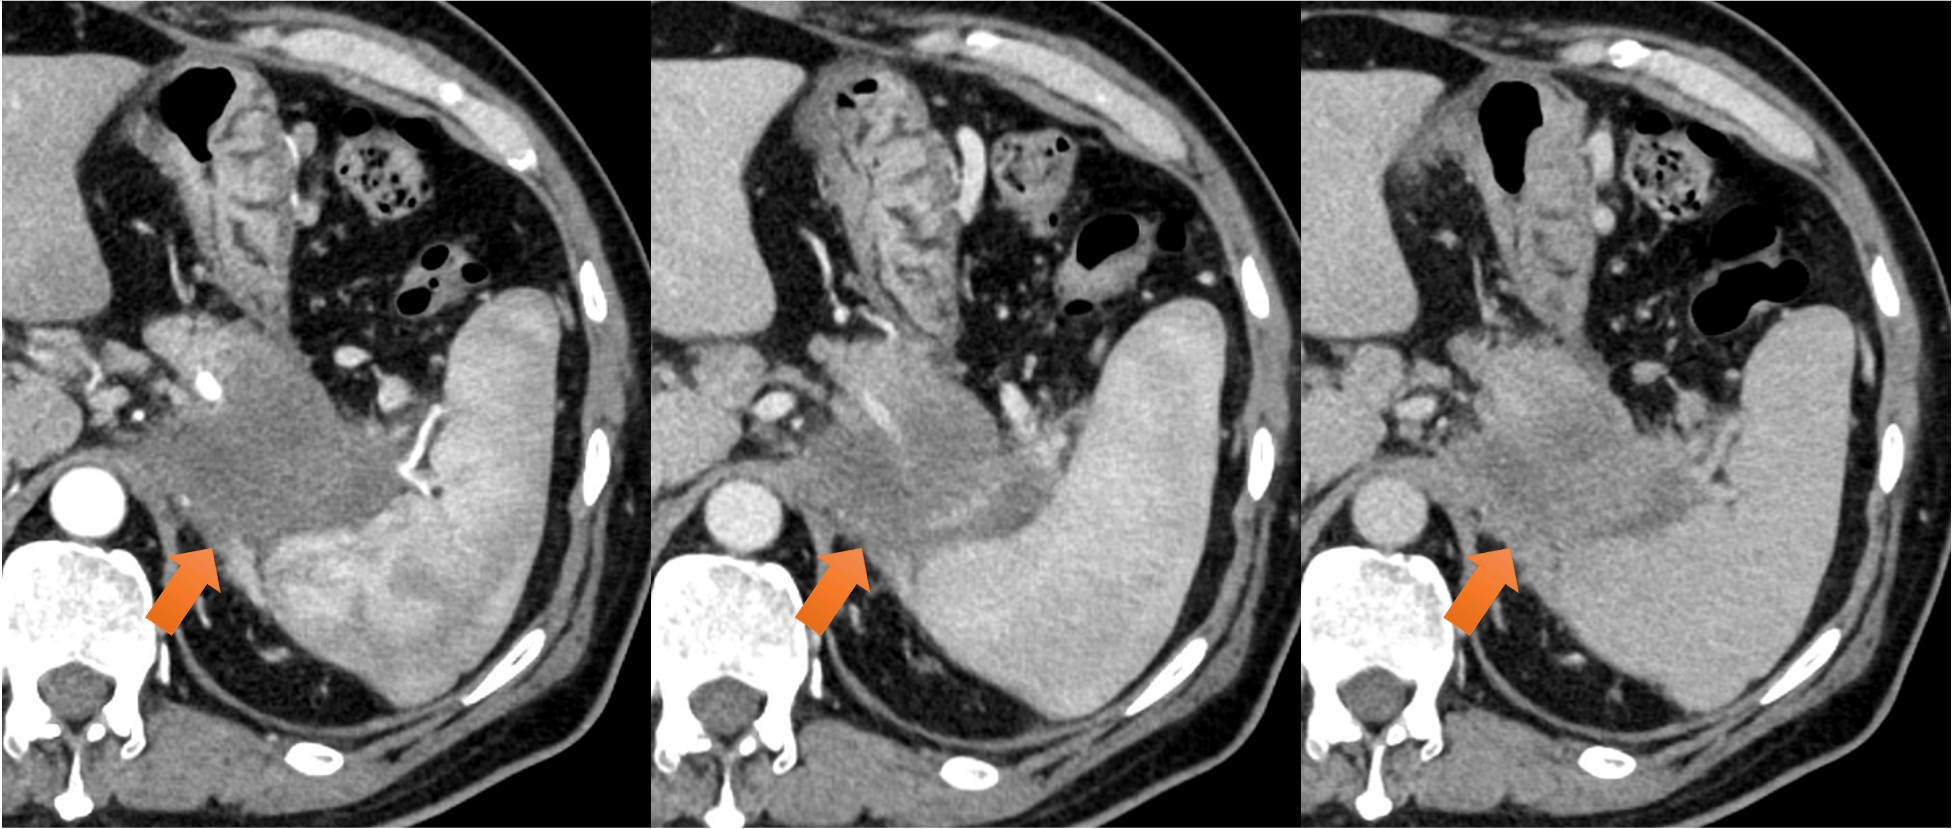

図2.周辺臓器浸潤

左横隔膜脚(→)、胃穹隆部~体上部、左副腎、脾臓、腹膜との間の脂肪織の消失を認めた。

図3.脾動静脈浸潤

脾静脈は腫瘍により閉塞しており(→)、脾動脈は腫瘍と全周性に接触し、口径不整を認めた(⇨)。